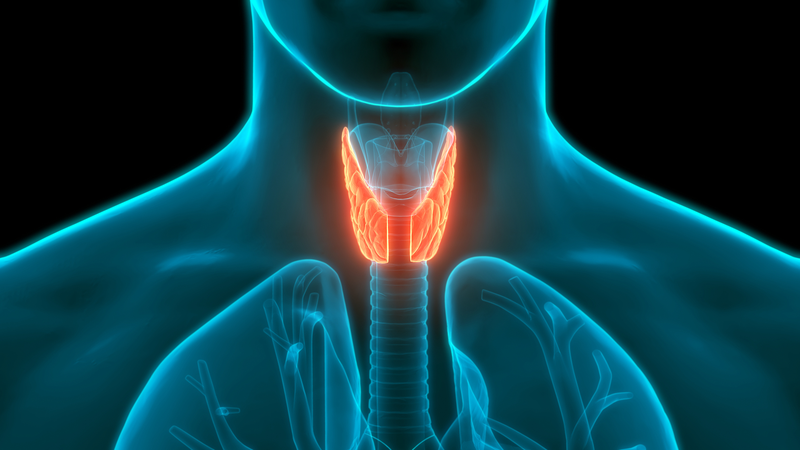

Thyroid health is taking a spotlight in the Chinese mainland as more young people join the conversation on personal wellness. A 24-year-old teacher named Joan Chen ignited this dialogue on the popular platform Xiaohongshu with a candid 2022 post about her battle with hyperthyroidism.

In her post, Joan detailed how the condition led to notable changes—bulging eyes, neck swelling, and even a 10-kilogram weight gain from her medication. More than just the physical symptoms, her honest disclosure about feeling emotionally withdrawn and losing confidence resonated with thousands of users, turning her thread into a vibrant support hub where many share their own thyroid-related experiences.

This surge in awareness marks a shift in how endocrine issues are perceived, especially among young professionals and early adults across the Chinese mainland. It’s a powerful reminder that sharing personal struggles can break barriers and foster a community of care and understanding. 💪😊